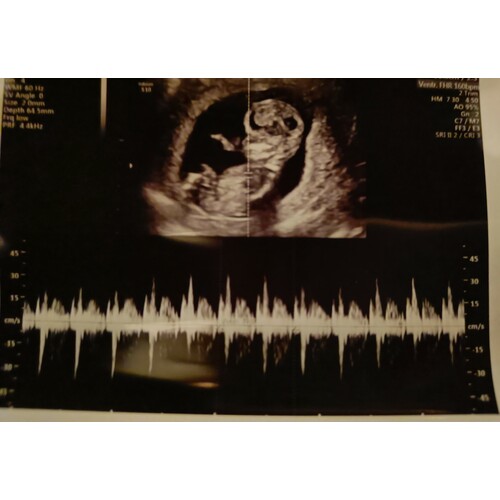

Ik heb hieronder een foto van ons kindje met T18 geplaatst. Ik vind dat hij er ‘afwijkend’ uitziet op de echo. Ik ben nu zwanger van een gezond jongetje en ik zie wel degelijk verschil als ik de echo’s met elkaar vergelijk. Ook als ik jouw echo bekijk, die ziet er in mijn ogen heel normaal uit allemaal.